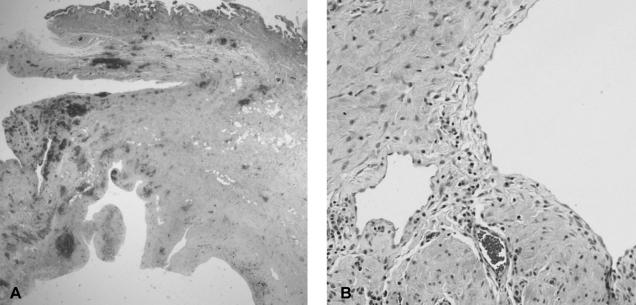

Cystic lymphangioma of the gallbladder is quite a rare tumor with only a few cases having been reported in the literature. We describe here a rare case of cystic lymphangioma of the gallbladder, which was unusual in that the patient presented with biliary pain and an abnormal liver test. Ultrasonography and computed tomography of the abdomen showed a multi-septated cystic mass in the gallbladder fossa and an adjacent compressed gallbladder. Endoscopic retrograde cholangiography showed there was no communication between the bile tract and the lesion, and there were no other abnormal findings with the exception of a laterally compressed gallbladder. After performing endoscopic sphincterotomy, a small amount of sludge was released from the bile duct. The histological findings were consistent with a cystic lymphangioma originating from the subserosal layer of the gallbladder. This unusual clinical presentation of a gallbladder cystic lymphangioma was attributed to biliary sludge, and this was induced by gallbladder dysfunction that was possibly from compression of the gallbladder due to the mass.

胆囊囊性淋巴管瘤是一种非常罕见的肿瘤,文献中仅报道过少数病例。我们在此描述一例罕见的胆囊囊性淋巴管瘤病例,该病例不同寻常之处在于患者表现为胆绞痛和肝功能检查异常。腹部超声和计算机断层扫描显示胆囊窝有一个多分隔的囊性肿块以及相邻的受压胆囊。内镜逆行胆管造影显示胆道与病变之间没有连通,除了胆囊侧向受压外没有其他异常发现。在内镜下进行括约肌切开术后,从胆管中排出了少量胆泥。组织学检查结果与起源于胆囊浆膜下层的囊性淋巴管瘤一致。胆囊囊性淋巴管瘤这种不寻常的临床表现归因于胆泥,而胆泥是由胆囊功能障碍引起的,胆囊功能障碍可能是由于肿块对胆囊的压迫所致。